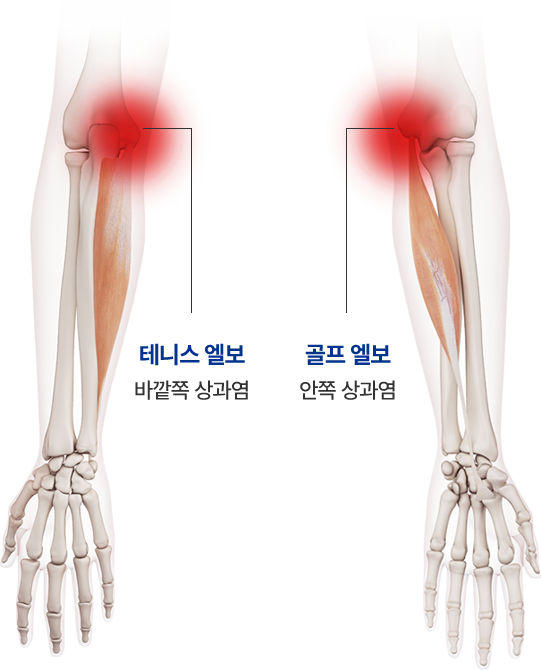

테니스·골프 엘보란 팔꿈치 통증을 유발하는 가장 흔한 퇴행성 질환으로 팔꿈치 근육이 시작되는 부위에 동통이나 압통이 느껴지는 증후군입니다.

팔꿈치 안쪽이 아프면 ‘골프 엘보’라고 합니다.